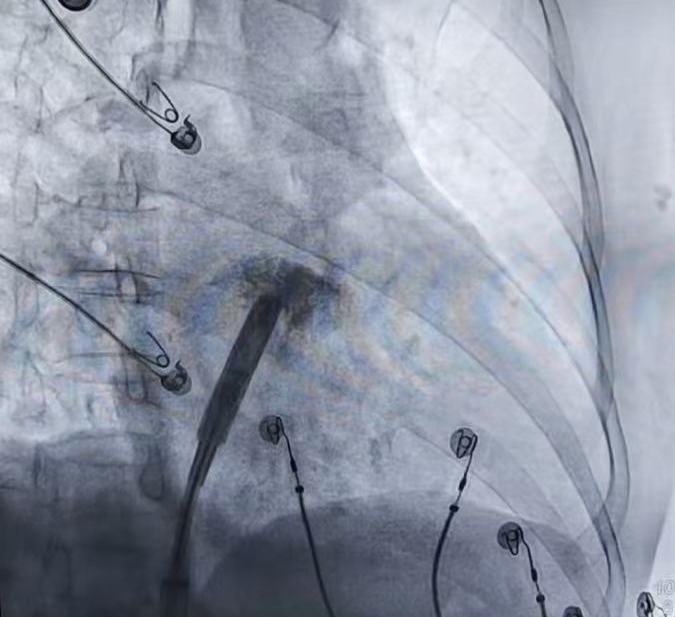

随后,团队将无导线起搏器通过可调弯的输送系统,判断位置合适后,回撤保护套筒至下腔,释放调弯,精准推送至右心耳基底部。术中分别采用RAO(右前斜)和LAO(左前斜)体位造影,确认器械头端位置理想后,进行电学参数标测。

术中释放无导线起搏器后的影像

手术的关键一步是旋入固定。术者缓慢旋入起搏器头端的主动螺旋结构,分阶段测试参数,确保螺旋有效嵌入心肌组织。旋入至预定圈数后,进入对接栓模式进行牵拉张力测试,验证固定稳定性。最终测试参数优异,起搏器被成功释放,患者心跳即刻恢复稳定。整个手术过程不足40分钟,患者全程清醒,无明显不适。术后参数为:阈值:0.75 V / 0.4 ms 感知:1mV阻抗:300 Ω。